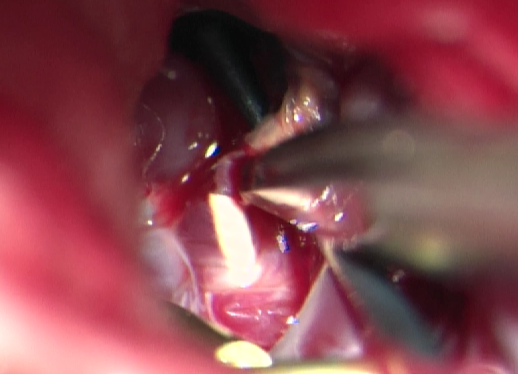

用Apollo微导管超选大脑中动脉M1段分支血管直至畸形团内,进行微导管造影确认微导管进入畸形团,DMSO冲管,缓慢注射Onyx 18,路图下可见胶在畸形团内弥散,最后颈内动脉造影可见畸形团完全不显影,但是胶反流导致拔管困难,透视下可见血管移位变形明显。

考虑到患者术前癫痫,且介入术中患者拔管困难,予以行开颅手术切除畸形血管团,并拔出微导管。术中可见微导管及注射的Onyx胶(血管内黄色部分及黑色部分),游离血管后近端用临时阻断夹阻断,远端剪断,打开临时阻断夹将微导管自股动脉鞘拔出,然后切除畸形团。术后复查头颅CT提示钙化及介入术中胶均已切除。